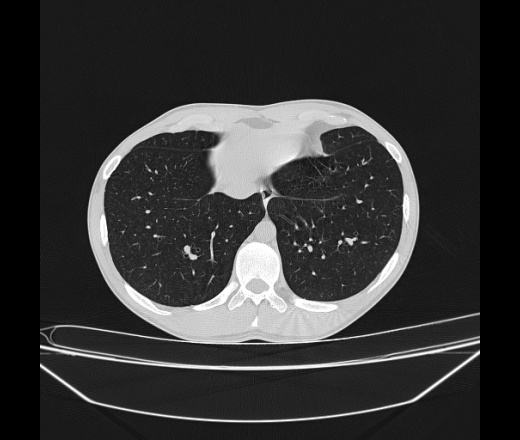

Молодой парень 18 лет, призывник, при прохождении ФЛС на верхушек левого легкого выявили очаги средней интснисвности с нечеткими контурами, тяжи. Сделали бок и томограммы 6-7-8. Везде описывают как очаговый твс. Вижу только перибронхиальный фиброз. Что за изменения в бронхах, указано нижи стрелками, тоже перибронхиальный?

Не стал бы говорить об очагах. Акцентировал бы не на фиброзе, а на тракционных бронхоэктазах. Не обязательно они результат tbc бронхов, но проверить не помешает.

Иван, пациент ведь уже "направлен с ОПТД", так?surprise Возвращайте его назад с заключением о возможном микобактериозе. Остаточные поствоспалительные ( посттуберкулёзные?) в дифряд.Очаговый твс с неясной активностью они уже себе "нарисовали", как я поняла.

+1 за микобактериоз.